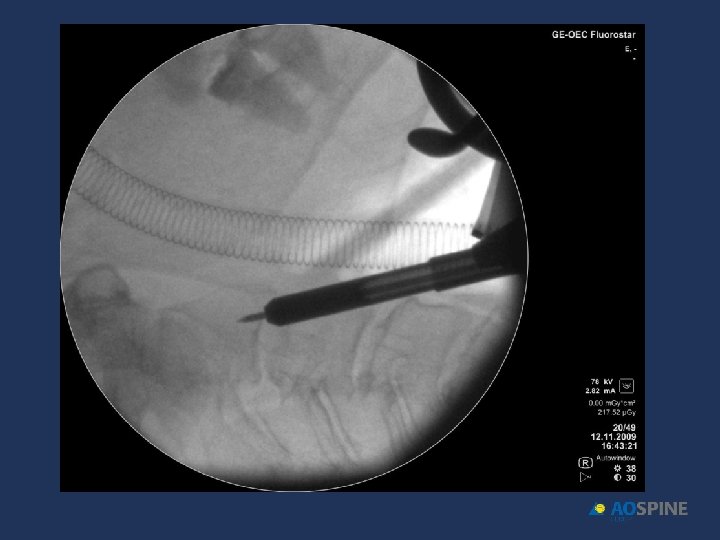

ODONTOID FRACTURES odontoid screw ADVANTAGES CONTRAINDICATIONS • PRESERVES MOTION C 1 C 2 • TRANSVERSE LIG RUPTURE • DONT NEED POSTOP HALO • EXTENSE C 2 BODY FX • DONT NEED BONE GRAFT • IRREDUCTIBLE FRACTURE • ANTERIOR OBLICUE FX

ODONTOID FRACTURES • RIGID COLLAR 10 -12 WEEKS • ONE SCREW • BEST RESULTS DURING FIRST 6 MONTHS AFTER FX Jenkins et al. J Neurosurg 1988, 89 Apfelbaum et al. J Neurosurg 2002, 93

ODONTOID FRACTURES odontoid screw • 90% FUSION TYPE II • 95% FUSION TYPE II < 6 MONTHS EVOL. • 100% FUSION TYPE III